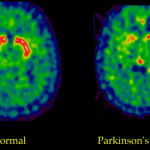

Il citomegalovirus, un virus che infetta la maggior parte delle persone, ma che di solito rimane inattivo nel corpo, potrebbe accelerare la progressione di una forma aggressiva di cancro al cervello quando particolari geni sono spenti nelle cellule tumorali, secondo nuova ricerca. Lo studio sugli  animali, condotto  da ricercatori della Ohio State University Comprehensive Cancer Center – Arthur G. James  e Richard J. Solove  al Dana Farber Cancer Institute, suggerisce che il citomegalovirus (CMV) potrebbe accelerare in modo significativo  lo sviluppo e la progressione del glioblastoma, una forma mortale di cancro al cervello.

Il citomegalovirus di per sé non provoca il cancro, secondo lo studio, ma potrebbe influenzare lo sviluppo del tumore, quando si verificano cambiamenti che silenziano due geni chiamati p53 e Nf1 nelle cellule tumorali. Questi geni sono “oncosoppressori” protettivi che normalmente inducono le cellule a morire prima che diventino maligne.Ma i cambiamenti legati al cancro possono farle tacere, consentendo alle cellule maligne di sopravvivere, moltiplicarsi e formare tumori.